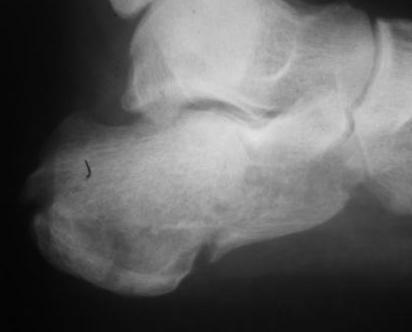

Операция проведена на 14е сутки после травмы. Фиксация блокируемой пластиной. Трудности - сложность репозиции; необходимость костной пластики (уложен измельченный трансплантат из гребня подвздошной кости 4,5х1,5х1см); множество мелких отломков; большой фрагмент наружной кортикальной пластинки, закрывающий картину в суставе.

followup1.jpg

По-моему, репозиция достигнута